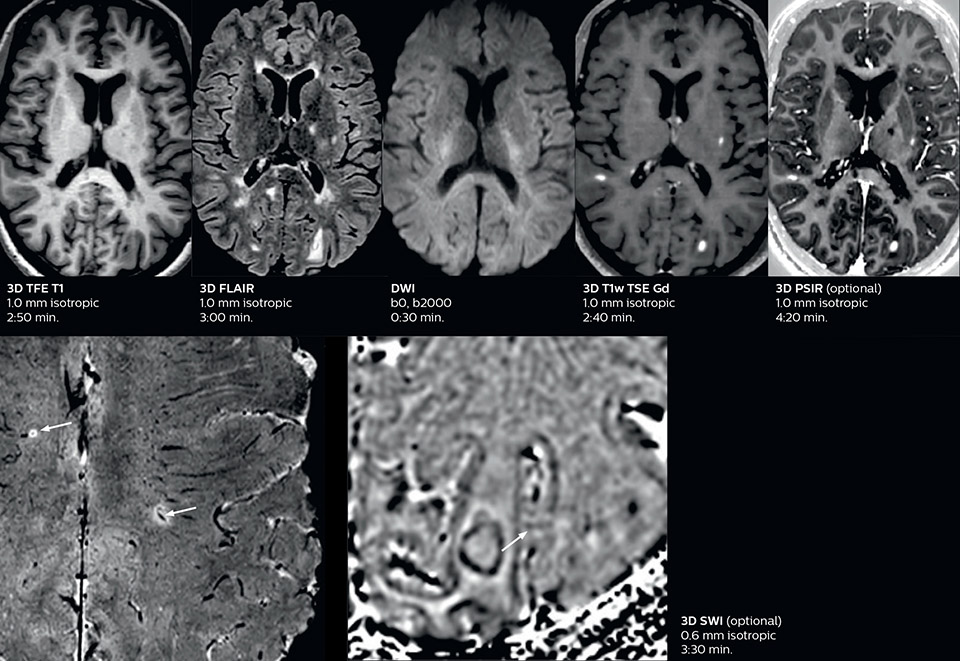

Fast MS protocol with optional sequences

The abbreviated MS protocol for brain is only around 9 minutes, so in case of suspected multiple sclerosis, one or two more advanced sequences may be added, such as PSIR (phase sensitive inversion recovery) or susceptibility-weighted sequences to help us make more confident diagnoses in these inflammatory cases.

In this example, the optional 3D multishot susceptibility weighted sequence with 0.6 mm isotropic voxels is 2 lesions with a central vein sign (arrows) and one lesion with a phase-rim sign (arrowhead). The total scan time, including SmartBrain and axial PD/T2 3mm, is 11:10 min. and is 18:30 min. with the optional 3D PSIR and 3D SWI multishot included.

3D TFE T1

3D FLAIR

DWI image

3D T1w TSE Gd

3D PSIR

3D SWI

“In multiple sclerosis patients, we increasingly include a multishot susceptibility sequence [3] in our routine cases, thanks to the shorter scan times. Our abbreviated MS protocol for brain is around 8 to 9 minutes, so we can ask for one or two additional sequences to visualize the central veins, or to get an additional contrast to better depict posterior fossa lesions. In cases of white matter lesions of unknown significance on FLAIR images, for example when we see high signal hyperintensities in the brain, we can add on more advanced sequences such as PSIR (phase sensitive inversion recovery) or susceptibility-weighted sequences to help us in distinguishing between MS and nonspecific or vascular abnormalities in these inflammatory cases.”